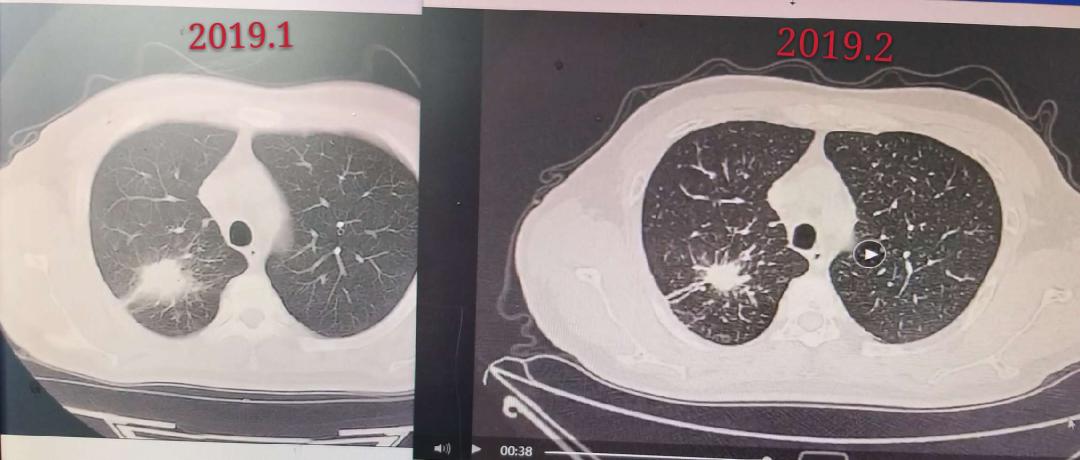

接着看下图,用药3个月后,2019年1月评估37mm×26mm,用药4个月后,2019年2月评估21mm*19mm,病灶持续缩小。

惊不惊喜?意不意外?Vv爸爸的假性进展缓解时间大概为1个月,在假性进展出现一个月后,第二次免疫评估时已经观测到了明显的缩小。容我插一段儿“煽情”:还记得取片子那天,是一个寒冷的冬夜,我开心得像个小兔子,一个人拿着爸爸的报告,坐着116公交车,没有目的地的,绕着整个城市好几圈,只知道哭,心里说不出的激动和开心,只要爸爸挺过这道难关,接下来一定都会好起来,超级好,无敌好,好到爆!